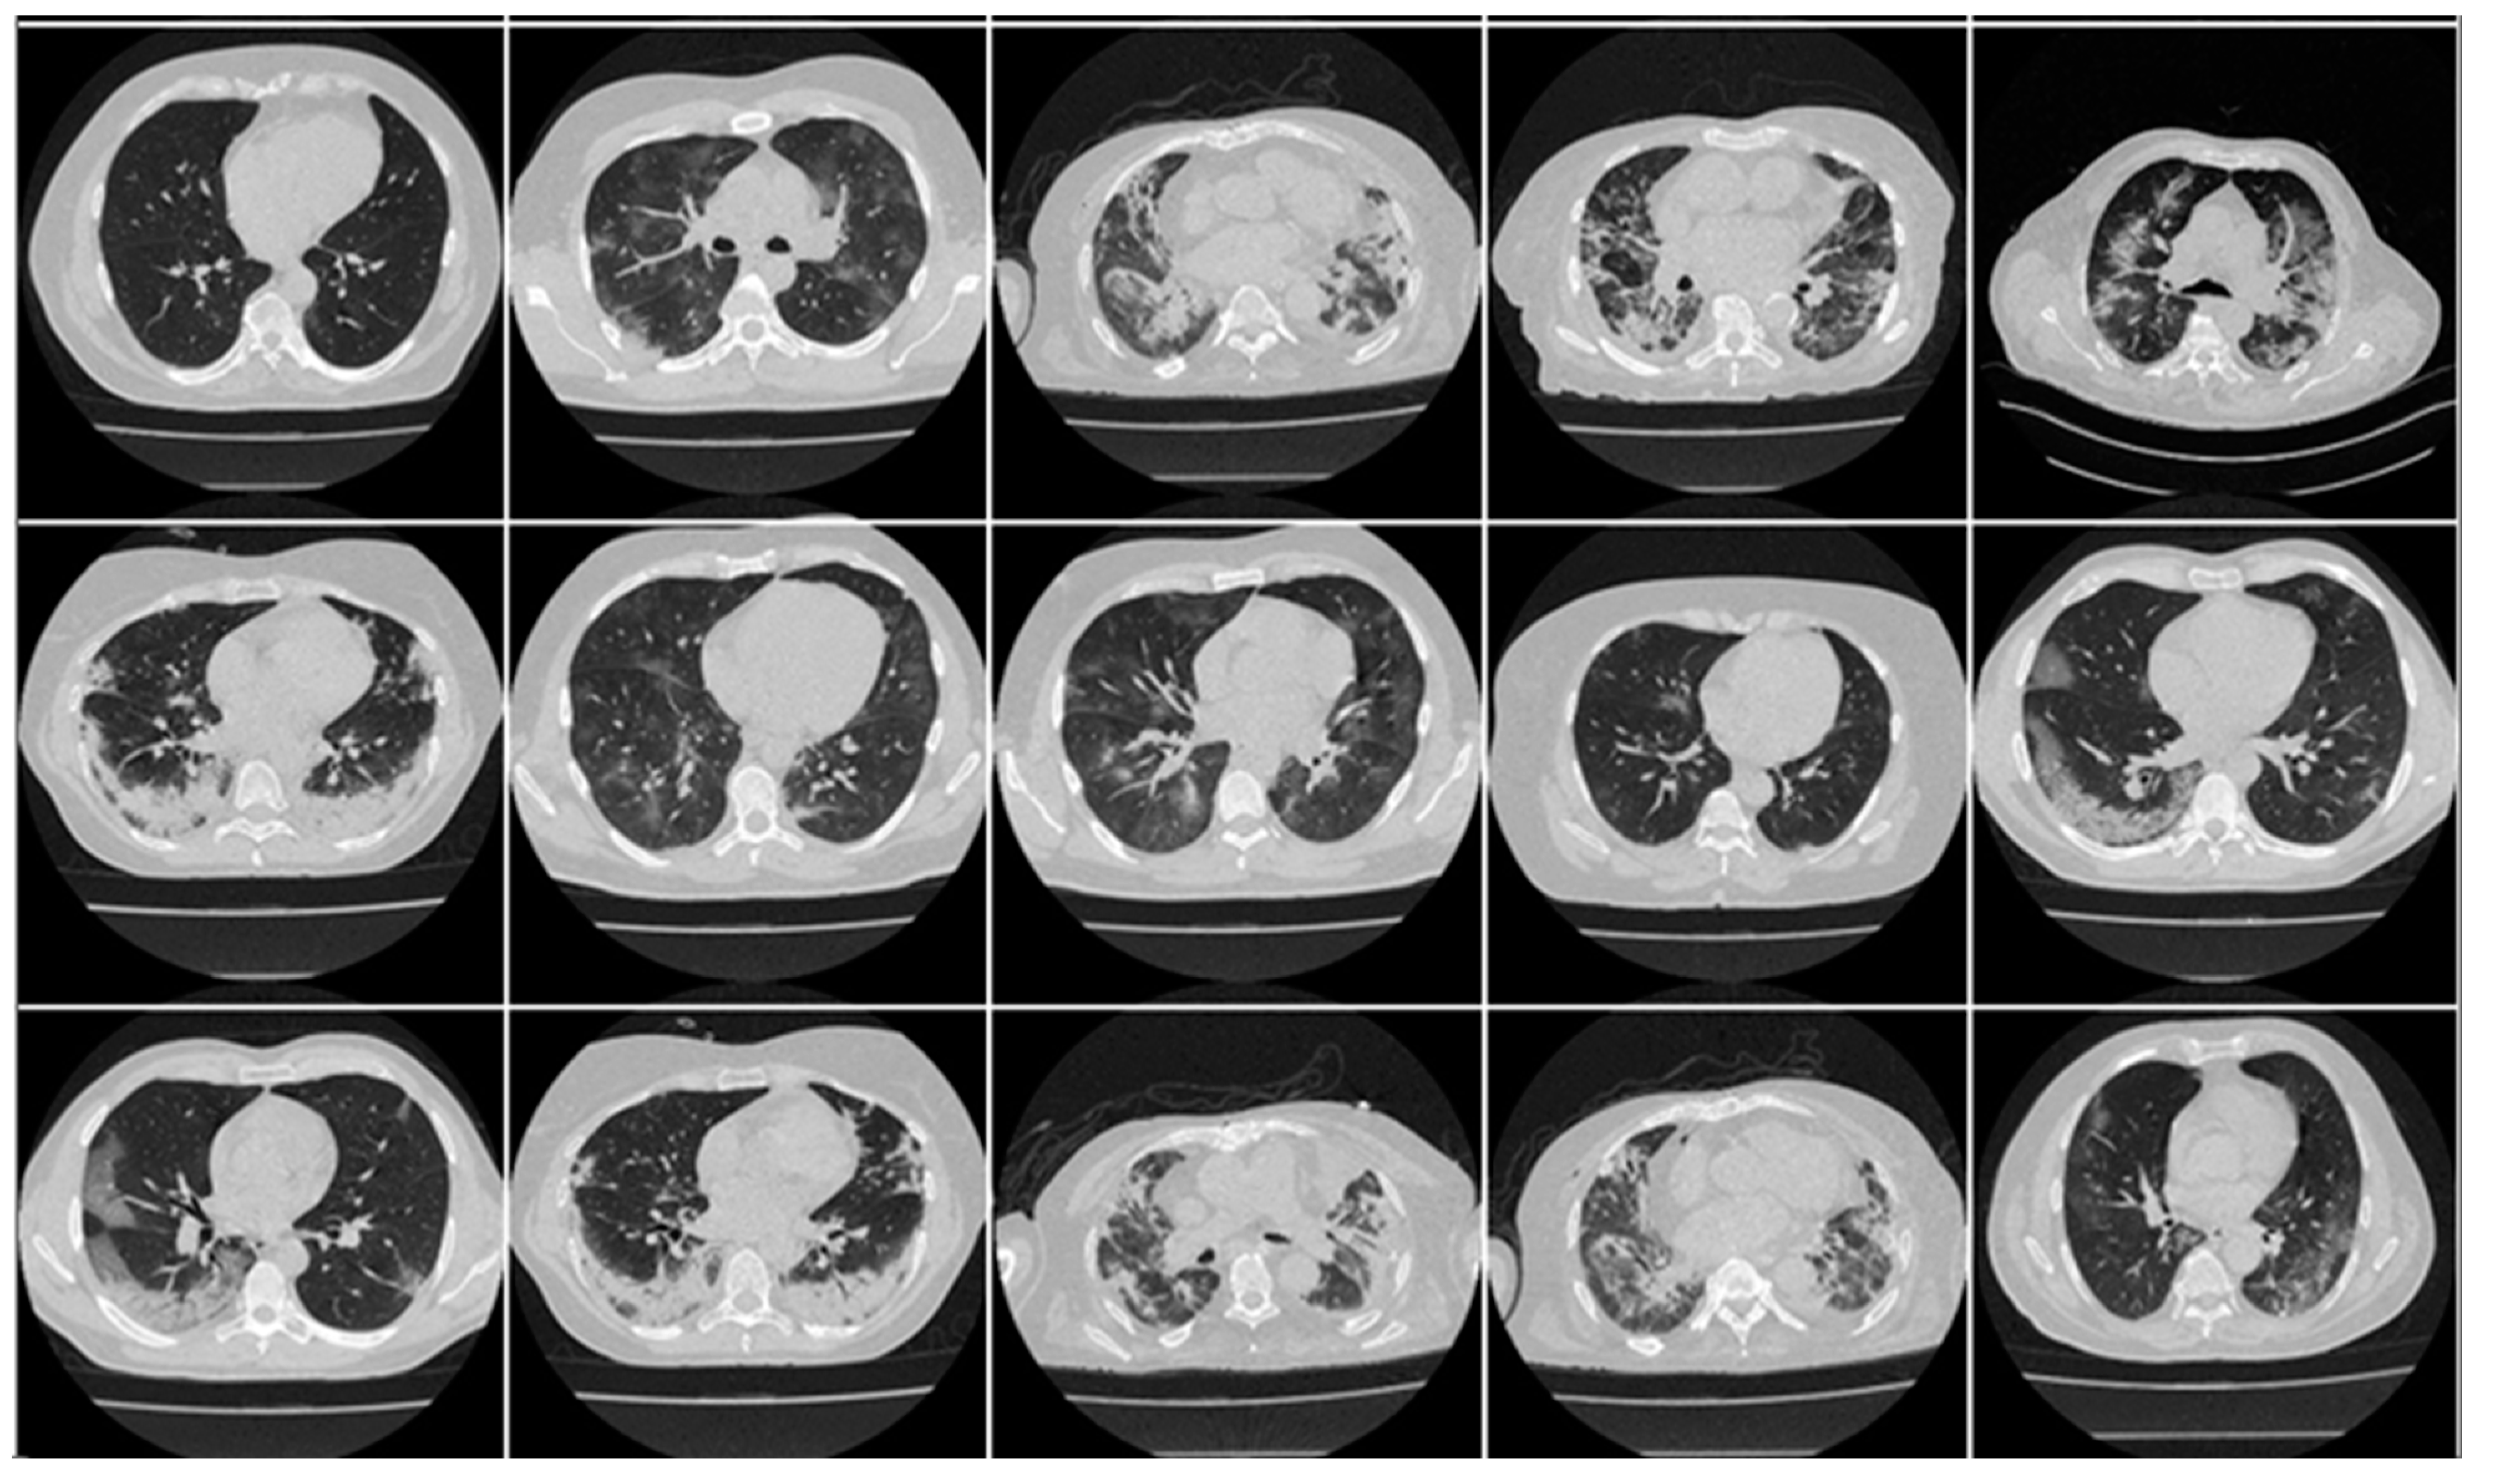

Appendix A

Appendix A includes three figures: Figure A1, Figure A2 and Figure A3. These diagrams are sample images of the dataset. Figure A1 is CroMED (COVID), Figure A2 depicts NovMED (COVID), and Figure A3 shows NovMED (Control).

Figure A1.

Raw “COVID-19 CT slices” taken from CroMED Dataset.